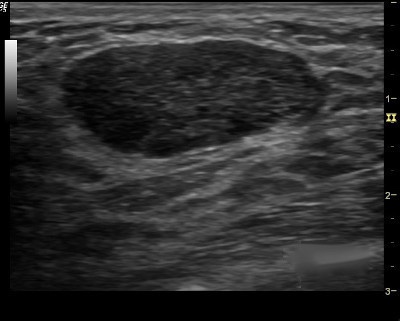

You first evaluate the lesion for any of the 10 malignant signs:

- Shadowing

- Hypoechoic echotexture

- Spiculation

- Angular margins

- Thick echogenic capsule

- Taller than wider

- Microlobulation

- Duct extension

- Branching pattern

- Calcifications

2. Finding none, you move on to the second step in the evaluation process and specifically look for one of the three strictly defined benign signs, and if any of them is found, the lesion can be considered BI-RADS 3.

3. The three benign findings defined by Stavros are:

- A purely hyperechoic lesion with no hypoechoic area larger than a normal duct or lobule.

- Elliptical, wider than tall, well-circumscribed and thin echogenic capsule.

- Gently lobulated, wider than tall, well-circumscribed and thin echogenic capsule.

– Combining the elliptical or gently lobulated shapes with the presence of a complete, thin echogenic capsule is necessary because many circumscribed carcinomas and most ductal carcinoma in situ are encompassed in a thin, echogenic capsule.